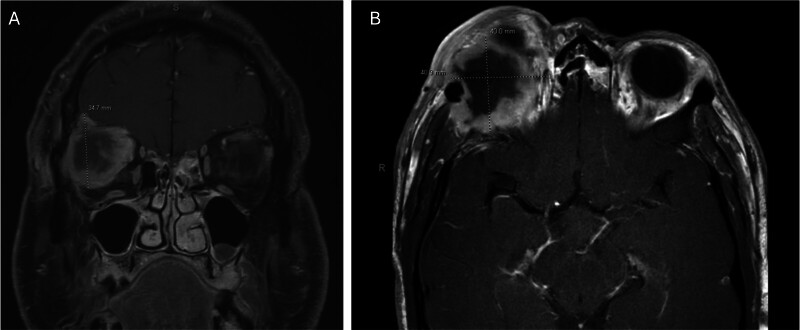

Carcinoma Ex-Pleomorphic Adenoma of the Lacrimal Gland with Intracranial Extension.

Carcinoma ex-pleomorphic adenoma (CXPA) of the lacrimal gland is rare, and its management can be complex given its anatomic location. In this case report, we describe our approach to multidisciplinary management of a CXPA with intracranial extension.